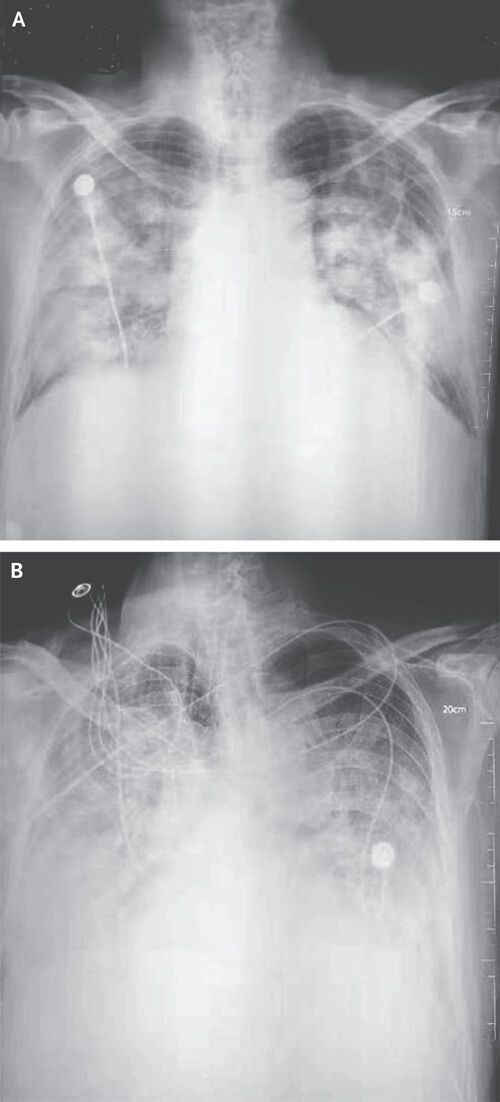

▲ 우한 폐렴 환자의 흉부 방사선 사진

AI가 검출할 수 있는 이상 소견은 ▲ 결절(폐에 생긴 작은 혹) ▲ 경화(폐 조직 일부가 딱딱하게 굳는 현상) ▲ 간질성 음영(폐 조직 사이의 공간에 이상이 생겨 X선 영상에서 비정상적으로 보이는 부분) ▲ 흉막삼출(폐를 둘러싼 막 사이 공간에 물이 차는 현상) ▲ 기흉(폐에 구멍이 생겨 공기가 새어 나오는 상태) 등 5가지 주요 질환입니다.

(사진=NEJM 논문 발췌, 연합뉴스)